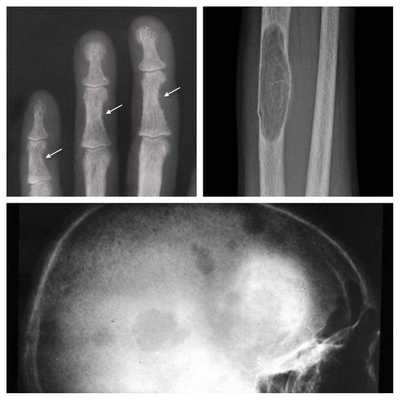

Длительное течение заболевания сказывается на формировании костей. Так, н а поздних стадиях вовремя не диагностированного гиперпаратиреоза наблюдаются:

- разрушение дистальных или концевых фаланг конечностей;

- сужение дистального отдела ключиц;

- очаги разрушения костей черепа;

- бурые опухоли длинных костей.

На поздней стадии костного гиперпаратиреоза происходит размягчение, искривления, патологические переломы (при обычных движениях, в постели) костей, возникают рассеянные боли в костях рук и ног, позвоночнике. В результате остеопороза челюстей расшатываются и выпадают здоровые зубы. Из-за деформации скелета больной может стать ниже ростом. Патологические переломы малоболезненны, но заживают очень медленно, часто с деформациями конечностей и образованием ложных суставов. На руках и ногах обнаруживаются периартикулярные кальцинаты. На шее в области паращитовидных желез можно пальпировать большую аденому.

Рентгенография позволяет обнаружить остеопороз, кистозные изменения костей, патологические переломы. Для оценки плотности костной ткани проводится денситометрия. При помощи рентгенологического исследования с контрастным веществом диагностируют возникающие при гиперпаратиреозе пептические язвы в желудочно-кишечном тракте. КТ почек и мочевыводящих путей выявляет камни. Рентгенотомография загрудинного пространства с пищеводным контрастированием бариевой взвесью позволяет выявить паратиреоаденому и ее местоположнение. Магнитно–резонансная томография по информативности превосходит КТ и УЗИ, визуализирует любую локализацию околощитовидных желез.